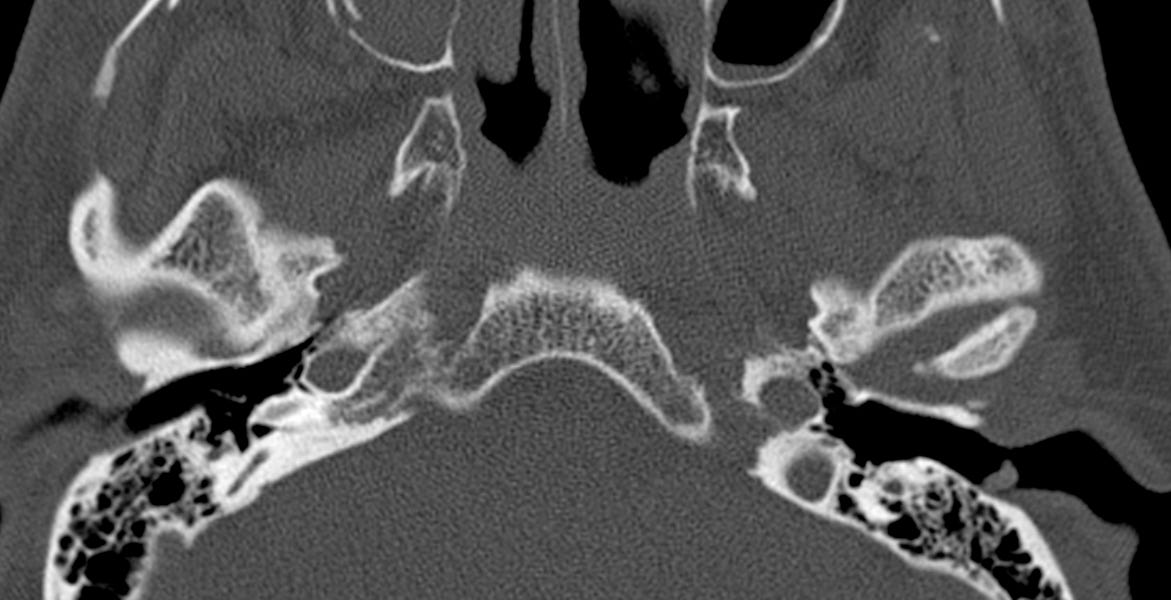

complex fracture Image Radiology Zygomaticomaxillary Complex Fracture the zygomaticomaxillary complex (zmc) has important aesthetic, structural, and functional roles that need to be. the detection of fractures of the facial zygomatic complex, with orbital compromise, is essential for surgical. zygomaticomaxillary complex (zmc) fractures result from blunt trauma to the periorbital area (viz. the zygoma and its articulations with. zygomaticomaxillary complex fracture is one. Radiology Zygomaticomaxillary Complex Fracture.

complex fracture Image Radiology Zygomaticomaxillary Complex Fracture zygomaticomaxillary complex (zmc) fractures result from blunt trauma to the periorbital area (viz. the zygomaticomaxillary complex (zmc) has important aesthetic, structural, and functional roles that need to be. zygomaticomaxillary complex fracture is characterised by fractures involving: the detection of fractures of the facial zygomatic complex, with orbital compromise, is essential for surgical. zygomatic complex fracture. Radiology Zygomaticomaxillary Complex Fracture.